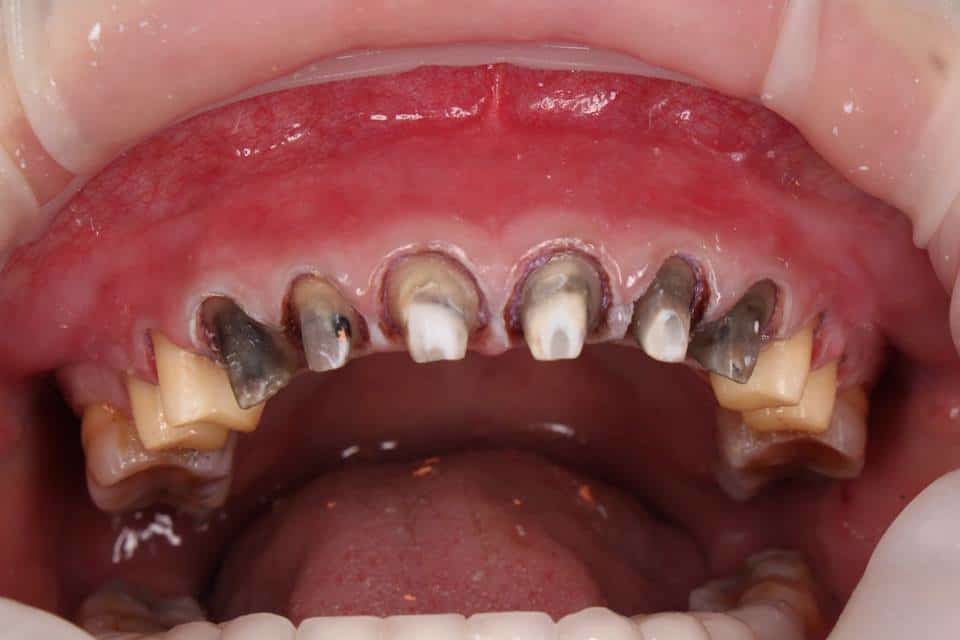

- Mão sứ không ôm sát khiến chân răng thật bị lộ. Theo thời gian chúng sẽ tạo điều kiện cho vi khuẩn phát triển.

- Có thể quan sát thấy phần lợi quanh chân răng đỏ, dễ chảy máu. Thậm chí dễ tụt lợi hoặc xuất hiện mủ nếu viêm nặng.

- Viền răng sứ không liền khít với mô nướu, tạo khoảng trống dễ tích tụ vi khuẩn và thức ăn.

Tuy nhiên, một số trường hợp bác sĩ thiếu kinh nghiệm hoặc tay nghề. Khi đó tỷ lệ mài không chính xác có thể gây ra tổn thương nghiêm trọng cho răng và nướu. Mài răng quá nhiều hoặc không đều dẫn đến tình trạng xâm lấn mô răng thật. Khi mô răng thật bị xấm lấn quá mức, nó sẽ làm suy yếu chân răng. Điều này không chỉ gây tụt nướu mà còn có thể gây ra dấu hiệu răng sứ có vấn đề. Từ đó ảnh hưởng đến cả tính thẩm mỹ lẫn chức năng ăn nhai của răng.

Các vật liệu kém chất lượng có thể gây kích ứng nướu. Từ đó dẫn đến tình trạng sưng tấy, viêm nhiễm. Thậm chí nó có thể làm răng sứ không ổn định trong miệng. Trong những trường hợp nghiêm trọng, răng sứ kém chất lượng có thể bị đẩy lên cao. Hoặc tạo ra khe hở với nướu, gây mất thẩm mỹ. Theo thời gian nó sẽ ảnh hưởng xấu đến sức khỏe răng miệng lâu dài.

Dấu hiệu răng sứ có vấn đề không chỉ ảnh hưởng đchức năng của răng miệng. Nó còn gây tác động nghiêm trọng đến tính thẩm mỹ của nụ cười. Lúc này, khoảng trống hoặc khe hở giữa răng sứ, cùi răng và nướu rất rõ. Theo thời gian điều này làm giảm sự đều đặn và hài hòa của hàm răng. Thông qua đó tạo ra một sự mất cân đối rõ rệt.

Những dấu hiệu răng sứ có vấn đề không chỉ làm mất tính thẩm mỹ. Đây là còn là môi trường lý tưởng cho vi khuẩn tích tụ. Khi vi khuẩn xâm nhập vào khu vực này, có thể gây ra các bệnh lý về nướu. Ví dụ như viêm nướu, viêm lợi hoặc nhiễm trùng. Nếu không được xử lý kịp thời, có thể dẫn đến các biến chứng nghiêm trọng hơn. Ví dụ như áp xe hoặc thậm chí mất răng. Vì vậy, việc duy trì sự khít chặt giữa răng sứ và cùi răng là yếu tố quan trọng. Thông qua đó phòng ngừa các vấn đề về viêm nhiễm. Đồng thời bảo vệ sức khỏe răng miệng lâu dài.